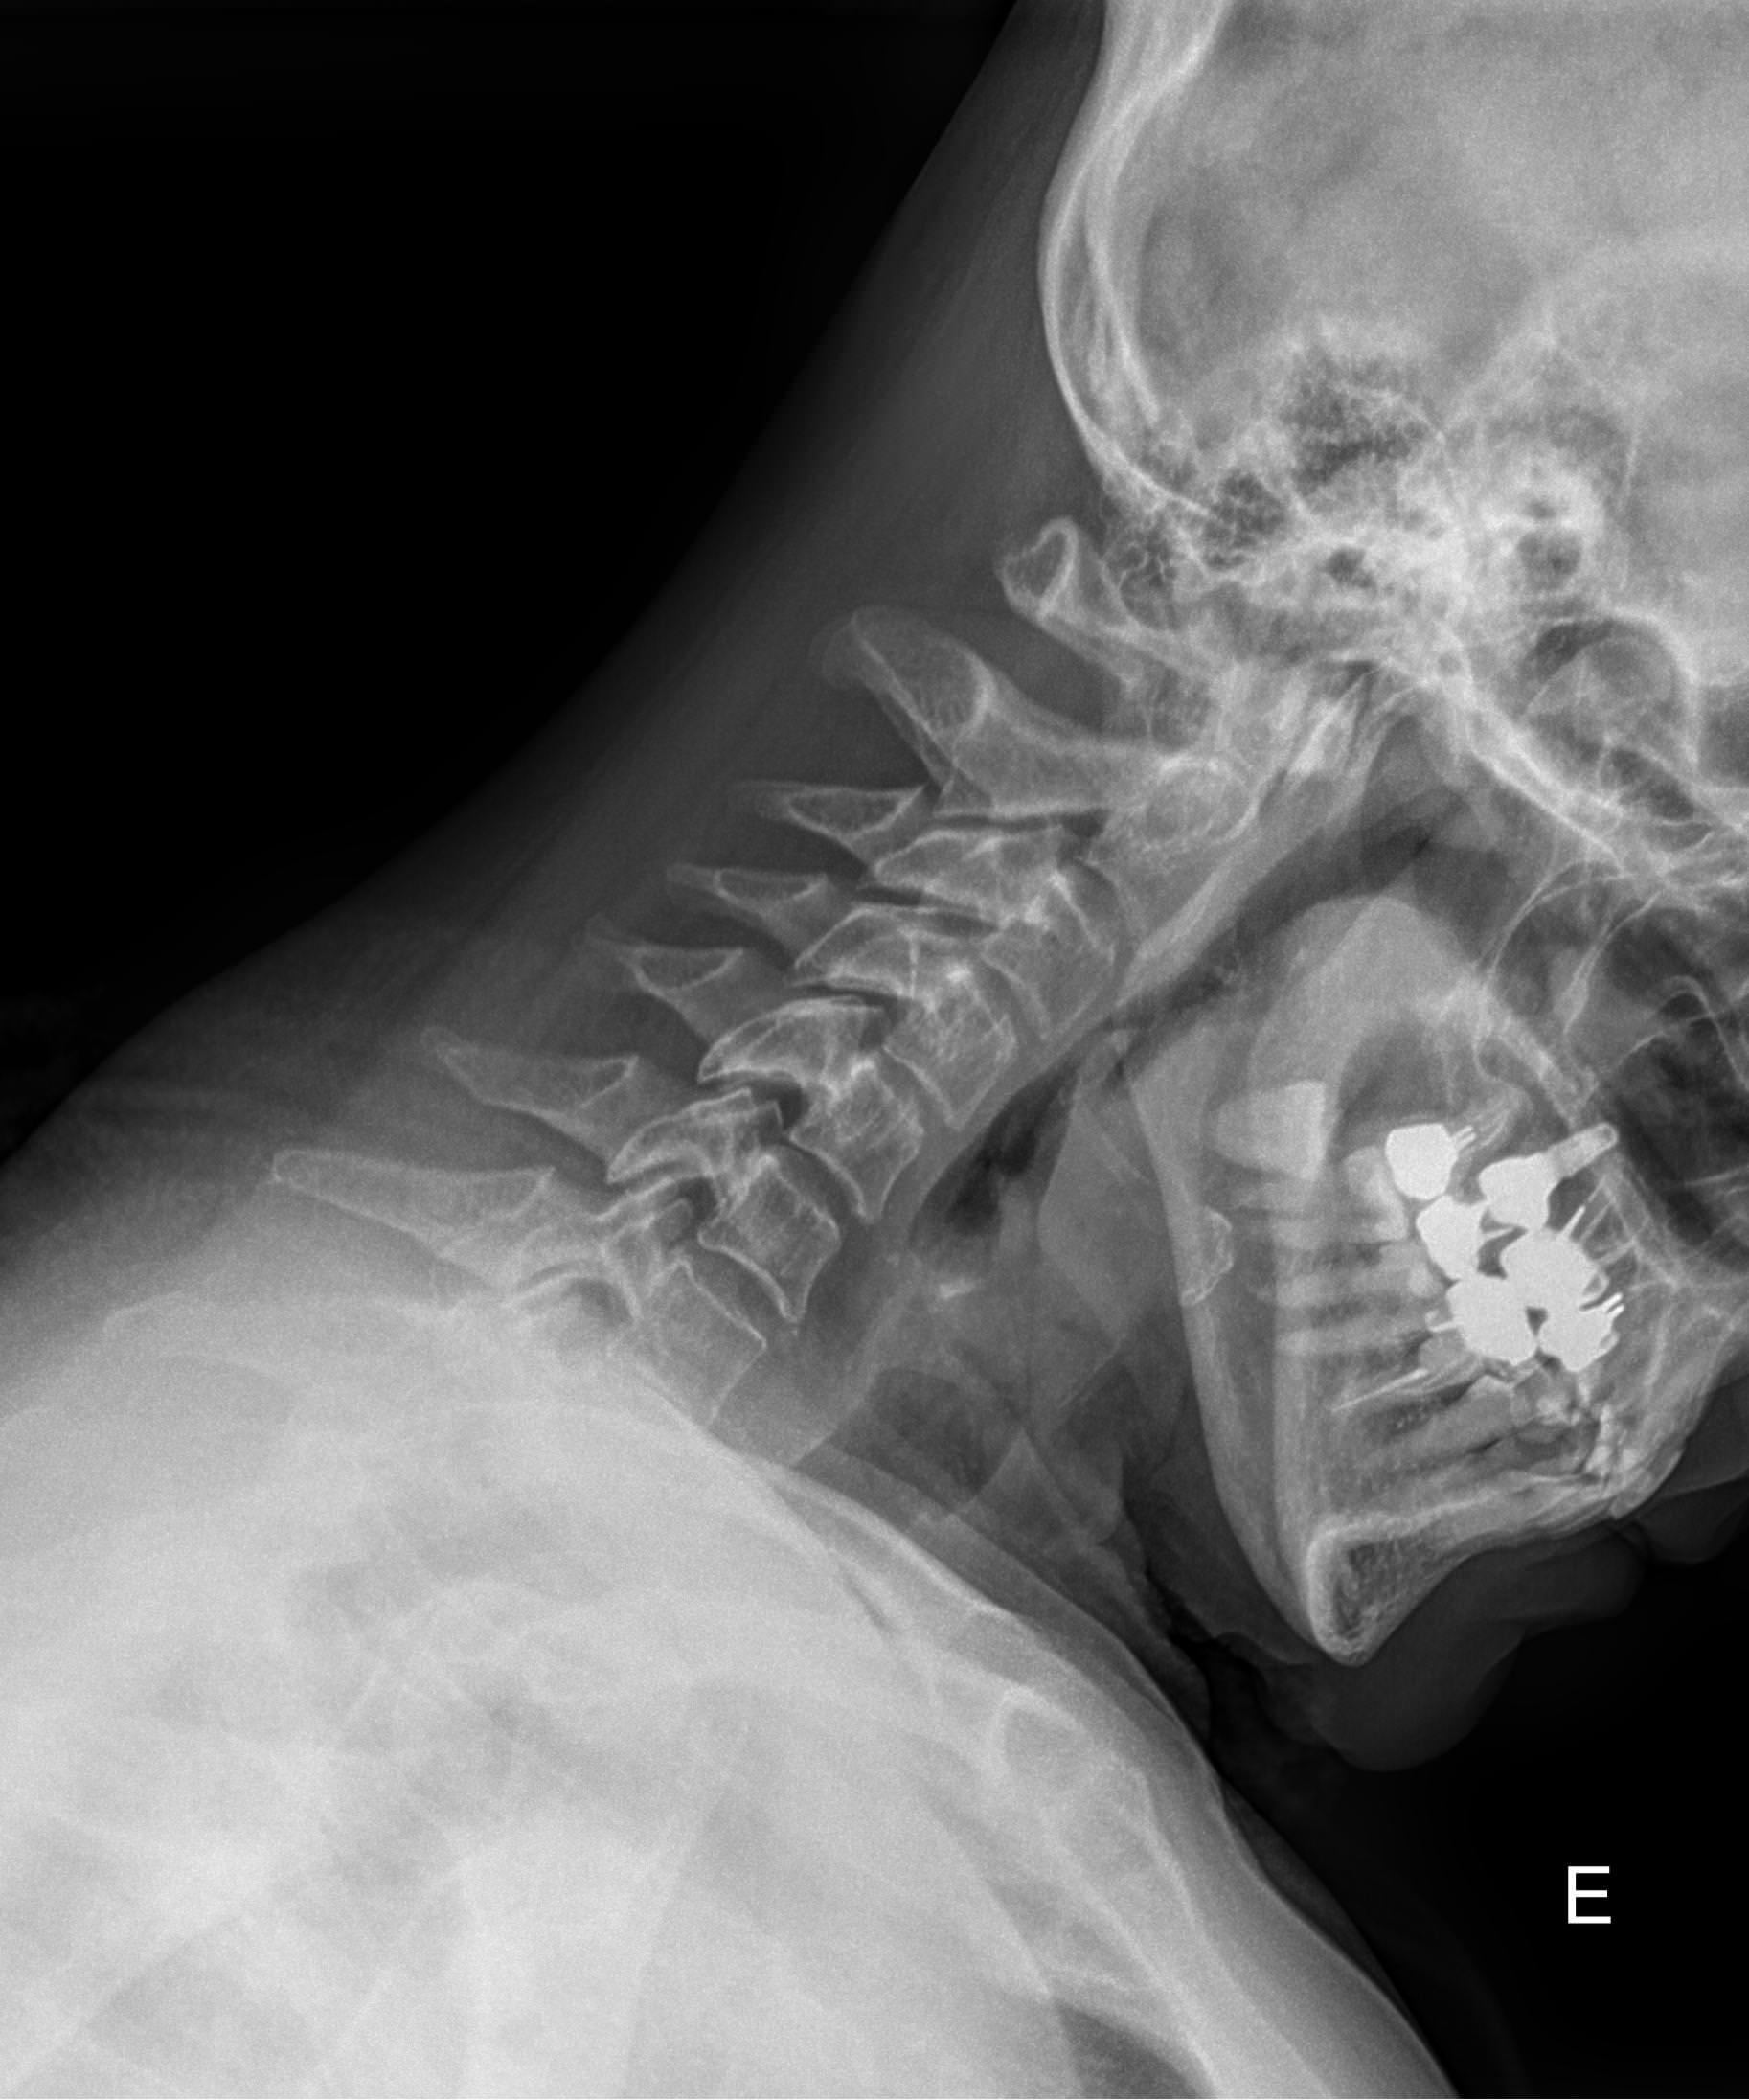

Функциональные исследования помогают выявить гипермобильность шейных позвонков или функциональный блок. Часто пробы позволяют определить начало остеохондроза, признаки которого на снимках в прямой и боковой проекции еще не заметны.

• Сохранение или сглаживание естественного лордоза в нейтральном положении, то есть на первом снимке;

• Смещение вперед или назад каждого позвонка по отношению к нижележащим при сгибании и разгибании;

• Деформацию передней стенки позвоночного канала из-за смещения позвонков;

• Сужения, расширения или отсутствие изменений межпозвоночных пространств;

• Изменения формы тел позвонков, наличие остеофитов;

• Аномалии развития.

В качестве подготовки необходимо снять все металлические украшения с шеи и головы, расстегнуть пуговицы и надеть защитную накидку. Диагностика выполняется в положении стоя или сидя, всего делается 3 снимка:

• В боковой проекции ― строго боком к детекторной пластине;

• В условиях максимального разгибания головы назад;

• В положении максимального наклона головы вперед.